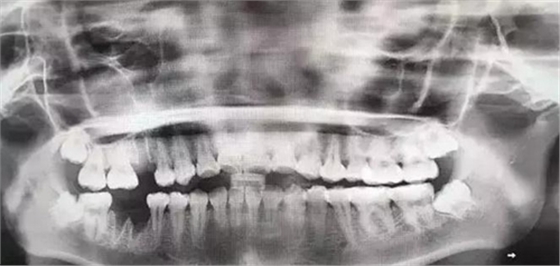

由于智齒的生長位置特殊,導(dǎo)致了拔除難易不同,如智齒出現(xiàn)橫著長或者靠近牙神經(jīng)的話,則難度會較高,一般人只需拍個口腔全景片,但相對于智齒靠近神經(jīng)管的情況,還可能需要拍CT,這都很考驗(yàn)牙醫(yī)的技術(shù)。

下面這兩張圖,據(jù)說拔牙費(fèi)時1.5小時,收費(fèi)14000元。